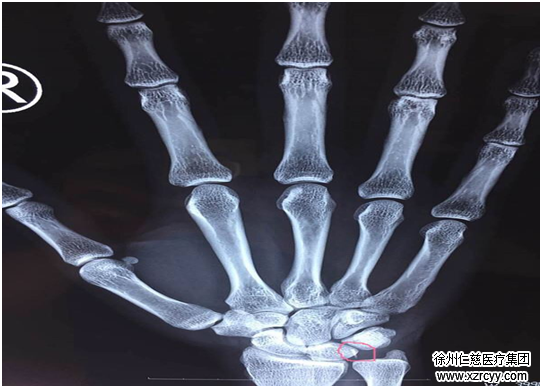

经过DR检查发现,其右手第5掌骨前缘皮质不连续,右手第4掌骨尺侧软组织内有异物留存。医生给小王开了点消炎药,建议他静养、休息观察一段时间,然后做个简单的异物取出术。

在X光的透视下,齐主任为小王进行了右腕部异物取出术,在小王的右腕部切开一个3厘米左右的小口,抽丝剥茧般将包裹在腕关节周围的神经及软骨组织一点点剥离,终于发现“潜伏”的异物,取出一看,竟然是一片指甲盖大小的玻璃碎片,困扰了小王半年之久的右手压痛终于彻底解决。